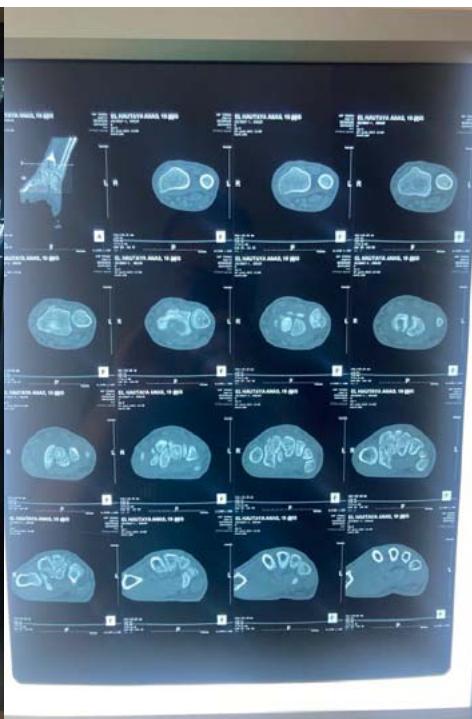

Marouane Dinia et al. Intraosseous Synovial Cysts of the Scaphoid Bone: A Rare Case of Fracture and Surgical Management